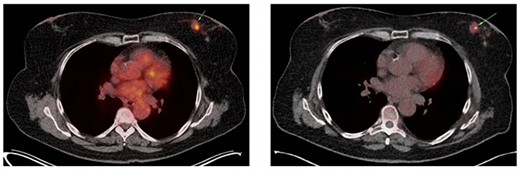

The patient was admitted to the emergency department 23 days after the oncoplastic breast surgery. She presented with abdominal pain, nausea, emesis and stool changes. General examination was normal and vital signs were normal except tachycardia. Abdominal distension, high-pitched tinkling bowel sounds and epigastric tenderness were observed. Laboratory tests revealed a white blood cell (WBC) count of 8.8*10E9/L and C-reactive protein (CRP) level of 19.4 mg/L. Abdominal computed tomography (CT) scan showed a short bowel obstruction caused by a stenosis in the terminal ileum and ileocecal junction without lymphadenopathy signs or metastasis. The basal lung segments were suspect for bilateral pulmonary embolisms (Fig. 2A–C), which was confirmed by a thoracic CT angiography. Retrospectively, an ileocecal tumor could not be identified on a follow-up PET/CT scan which was performed 7 weeks prior to emergency room presentation (Fig. 2D).

Coronal (A) and axial slice (B) of the abdominal CT scan at ER presentation showing small bowel obstruction with terminal ileum (green ellipse) and ileocecal junction stenosis. (C) CT scan at ER presentation also showed pulmonary embolisms in basal lung segments bilaterally (green ellipse). (2D) PET/CT performed 7 weeks prior to ER presentation showed no 18FDG uptake terminal ileum or ileocecal junction.